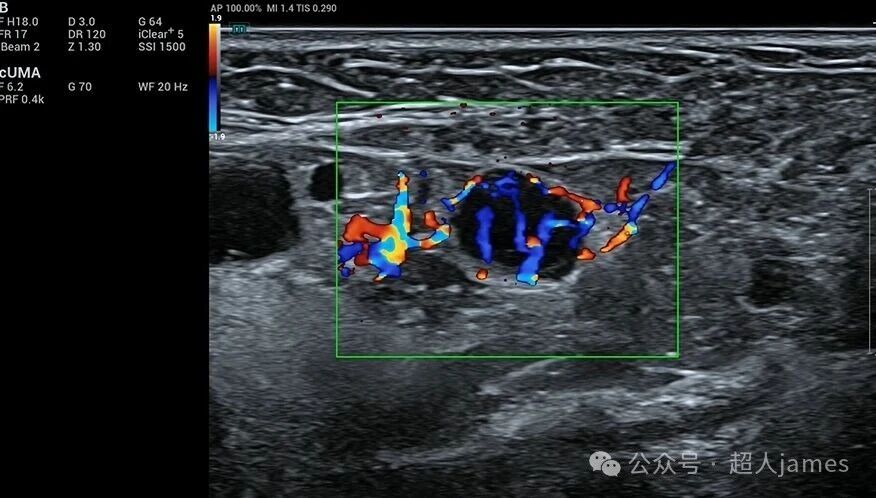

甲状腺微小癌也要警惕颈部淋巴结的转移

甲状腺微小癌也要警惕颈部淋巴结的转移,迈瑞超声

来源微信公众号“超人jams”